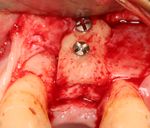

An incision is made across the area and the flap of gingiva is opened to show the bone of the jaw.

An incision is made across the gingiva, and the flap of tissue is reflected to show the bone of the jaw.

A series of slow-speed drills create and gradually enlarge a site in the jaw for the implant to be placed. The hole is called an osteotomy.

Once the bone is exposed, a series of drills create and gradually enlarge a site (called an osteotomy) for the implant to be placed.

The implant fixture is turned into the osteotomy. Ideally, it is completely covered by bone and has no movement within the bone.

A healing abutment is attached to the implant fixture and the gingiva flap is sutured around the healing abutment.

A healing abutment is attached to the implant fixture, and the flap of gingiva is sutured around the healing abutment.

يتم اجراء جراحة الأسنان في العيادة تحت ظروف معقمة، من قبل طبيب أسنان متخصص في زراعة الأسنان و/أو جراحة الفم والفك. يتم تخدير المريض بواسطة حقنة بمخدر موضعي في منطقة دواعم السن، كما هو الحال في علاجات الأسنان العادية (في بعض الأحيان هناك حاجة بتوسيع نطاق التخدير، وفقاً لموقع الغرسات).

اذا كان العظم على استعداد لتلقي الزرع (أحيانا بعد سلسلة علاجات مسبقة)، يمكن البدء بعملية زرع الاسنان. يتم تثبيت المسامير المعدنية اللولبيه براغي، بعظم الفك. في سلسلة اخرى من العلاجات بعد فترة من ادخال البراغي، تبدا عمليات اعادة البناء عن طريق أخذ القياسات وانشاء التاج/الجسر. عندما يدور الحديث عن فترة الانتظار بين تركيب الغرسات وبين تنفيذ الاستبناء النهائي، فان هنالك اكثر من نهج واحد. النهج المتبع غالبا هو الانتظار لمدة 6 أسابيع على الأقل حتى تلتئم الانسجة، وأحيانا تصل فترة الانتظار لعدة شهور.